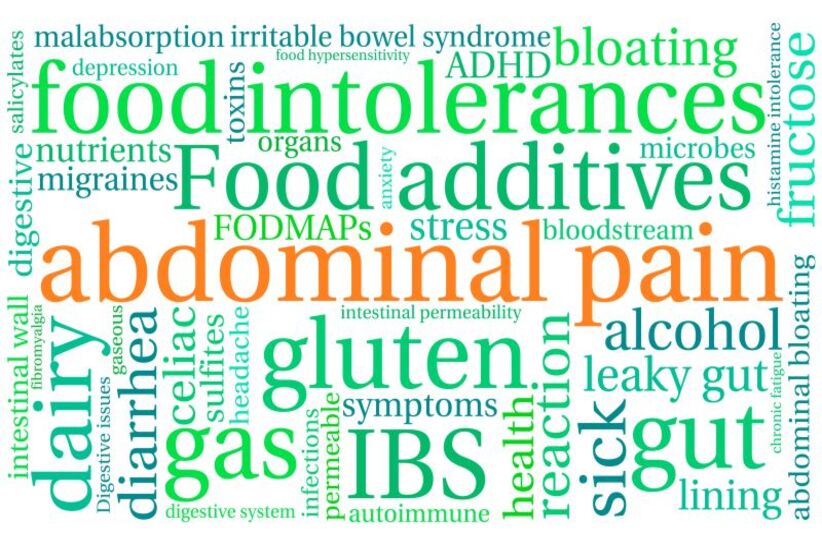

La inflamación se volvió un estado “normal” de nuestro cuerpo. Aunque la inflamación es una herramienta que utilizan nuestros tejidos

El “colon es irritable” se conoce por la aparición un dolor en el abdomen persistente pero casi siempre intermitente con

La inflamación se volvió un estado “normal” de nuestro cuerpo. Aunque la inflamación es una herramienta que utilizan nuestros tejidos

El “colon es irritable” se conoce por la aparición un dolor en el abdomen persistente pero casi siempre intermitente con